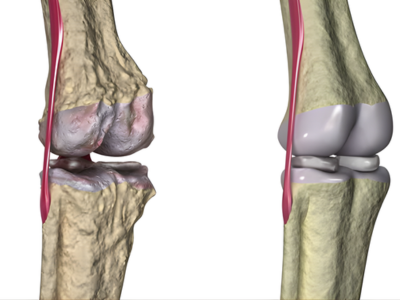

Arthritis

Management of osteoarthritis and rheumatoid arthritis to reduce pain, improve joint function, and enhance mobility.

Degenerative joint diseases

Treatment for age-related joint wear and tear to improve comfort and quality of life.

1. How long is the recovery after joint replacement surgery?

Recovery varies, but most patients begin walking within days and return to routine activities within a few months.